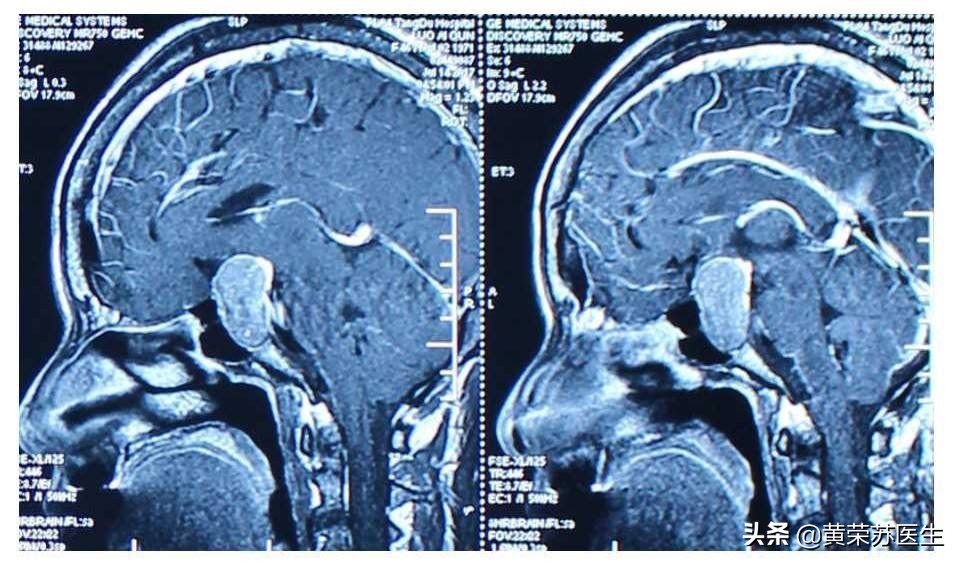

依据:有人担心妊娠期间泌乳素大腺瘤会增大,而微腺瘤增大的可能性较小。患者会被告知确诊妊娠后应停用多巴胺激动剂,而前期治疗缩小的垂体瘤也会长大。妊娠期间高浓度雌激素会刺激正常垂体内的泌乳素细胞增生,这种生理性的垂体生长会造成垂体瘤向鞍区之外发展。同时,高浓度雌激素环境会直接促进泌乳素瘤生长。实际上,在一般情况下,鞍区内的泌乳素微腺瘤和大腺瘤不会出现增大的症状。一篇包括457例微腺瘤的妊娠患者的综述指出,仅2.6%的患者出现垂体瘤增大的症状。由于垂体瘤增大而出现症状的风险很低,微腺瘤患者仅需在妊娠期间每3个月作一次体检;而大腺瘤增长出现症状的风险则大得多。妊娠前接受过垂体减压手术或垂体放射治疗的患者,妊娠期间出现垂体瘤增长症状的仅占2.8%,与微腺瘤患者的风险无差异。妊娠前未做手术或放射治疗的大腺瘤患者,垂体瘤增长而出现症状的风险高达31%。如果发生头痛或头痛症状加重、视野改变,应立即作正规的视野检查和垂体磁共振(避免用钆同位素)。